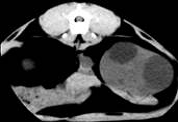

Комп’ютерна томографія нирок у домашніх собак

і кішок,

хворих на полікистоз. Враховуючи той факт, що в

доступній спеціальній літературі не вдалося знайти повідомлень щодо

застосування методу комп’ютерної томографії для діагностики ренальних патологій

у кішок, ми у своїй роботі вважали актуальним вивчення цього питання.

Комп’ютерну томографію застосовували, попередньо

встановивши діагноз з використанням загальних методів, ультрасонографії та

лабораторних досліджень. Дослідження здійснювали за допомогою покрокового

комп’ютерного томографу фірми «Siemens»

Somaton CR-X.

Тварин розміщували на рухомому столі приладу у спинно-черевному положенні, так

щоб під час процедури напрямок руху був краніо-каудальним. Забезпечували

належну фіксацію пацієнта. Томографію проводили при параметрах приладу 120 кV,

80mА у аксіальній

проекції. Визначивши краніальний полюс правої нирки, розпочинали сканування з

інтервалом 3-5 мм, аж до каудального полюсу лівої нирки. Результати аналізували

за допомогою комп’ютера та графічно.

За отриманими даними, полікистозні ураження обох

органів візуалізувались на томограмі у вигляді округлих утворень різної

щільності за шкалою Хаунсфілда, що певною мірою залежить від характеру вмісту

кіст (мал). Так, відносна гіподенсність (10-20 HU)

порожнини кіст може свідчити про низький вміст органічних речовин, що в свою

чергу можна характеризувати як неускладнений перебіг полікистозу. Більш висока

інтенсивність сигналу (50-60 HU)

свідчить про крововилив у кісту. Зростання інтенсивності сигналу у цьому разі,

очевидно, спричинене високим вмістом заліза у гемоглобіні, що й зумовлює зміни

парамагнітних властивостей середовища.

Рис.6. Серія КТ

сканів нирок кота. Кисти нирок, більше зліва